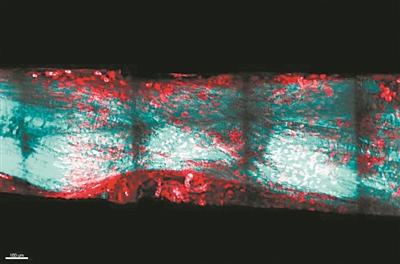

團隊調查了後足中趾受傷的屈肌腱,這是蠑螈和小鼠常見的身體部位。他們發現,受傷後6周,蠑螈已長出了類似於肌腱的新組織;在12周時,再生的組織顯示出與健康肌腱相當的強度,並且完全沒有疤痕。然而在小鼠中,即使在12周時,其強度仍低於健康肌腱的強度。

研究表明,肌腱樣膠原組織橋接了蠑螈的肌腱殘端。這與小鼠受傷區域充滿雜亂的疤痕樣組織不同。團隊還觀察到,蠑螈新形成的腱和殘留腱的交界處,有更多的細胞核。由於細胞數量與細胞生長相關,跟蹤它們是瞭解蠑螈肌腱再生機制的關鍵。